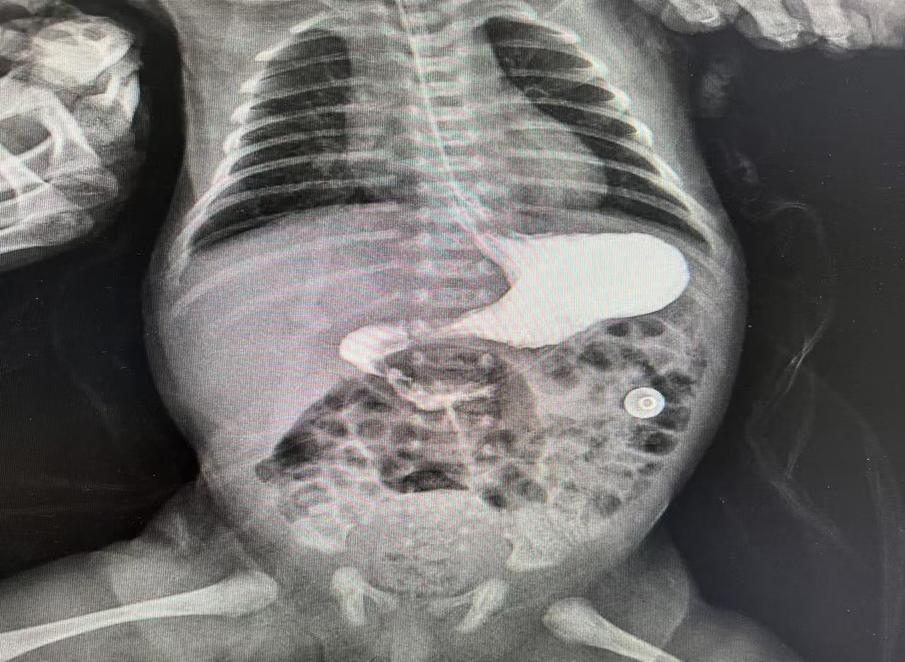

分娩將至���,陳女士來(lái)到衡陽(yáng)市中心醫(yī)院待產(chǎn)����。醫(yī)院高度重視,組織多學(xué)科聯(lián)合會(huì)診��,確定分娩方式���,嚴(yán)密觀察產(chǎn)婦情況�。1月11日下午���,陳女士足月剖產(chǎn)一名3.44KG的男嬰����,出生后頻繁嘔吐�,隨即轉(zhuǎn)入新生兒科進(jìn)行監(jiān)護(hù)����。主管醫(yī)生許承輝立即給患兒下胃管進(jìn)行胃腸減壓、全靜脈營(yíng)養(yǎng)��,同時(shí)進(jìn)行上消化道造影檢查�����,進(jìn)一步明確了患兒十二指腸閉鎖的診斷�。隨即新生兒科主任雷明、副主任王紅燕立即組織MDT聯(lián)合診治,制定最佳手術(shù)方案�,充分術(shù)前評(píng)估,完善術(shù)前準(zhǔn)備�����。

術(shù)前造影提示十二指腸遠(yuǎn)端閉鎖